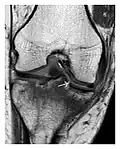

- a

- b

- c

Figure 8: Proximal diaphyseal fatigue fracture of the tibia in a 20-year-old man with a history of regular jogging. (a) Lateral radiograph shows no obvious fracture lines but a subtle localized medial tibial cortex periosteal reaction (arrows). (b) Sagittal reformatted CT image acquired 1-month after the radiograph shows a linear hypoattenuation in the tibial cortex (arrowhead), as well as obvious periosteal thickening (arrows). (c) Sagittal T2-weighted fat-saturated image acquired the same day shows an area of hyperintensity spreading over the proximal tibia (arrows), which is consistent with the presence of proximal tibial fracture.[1]